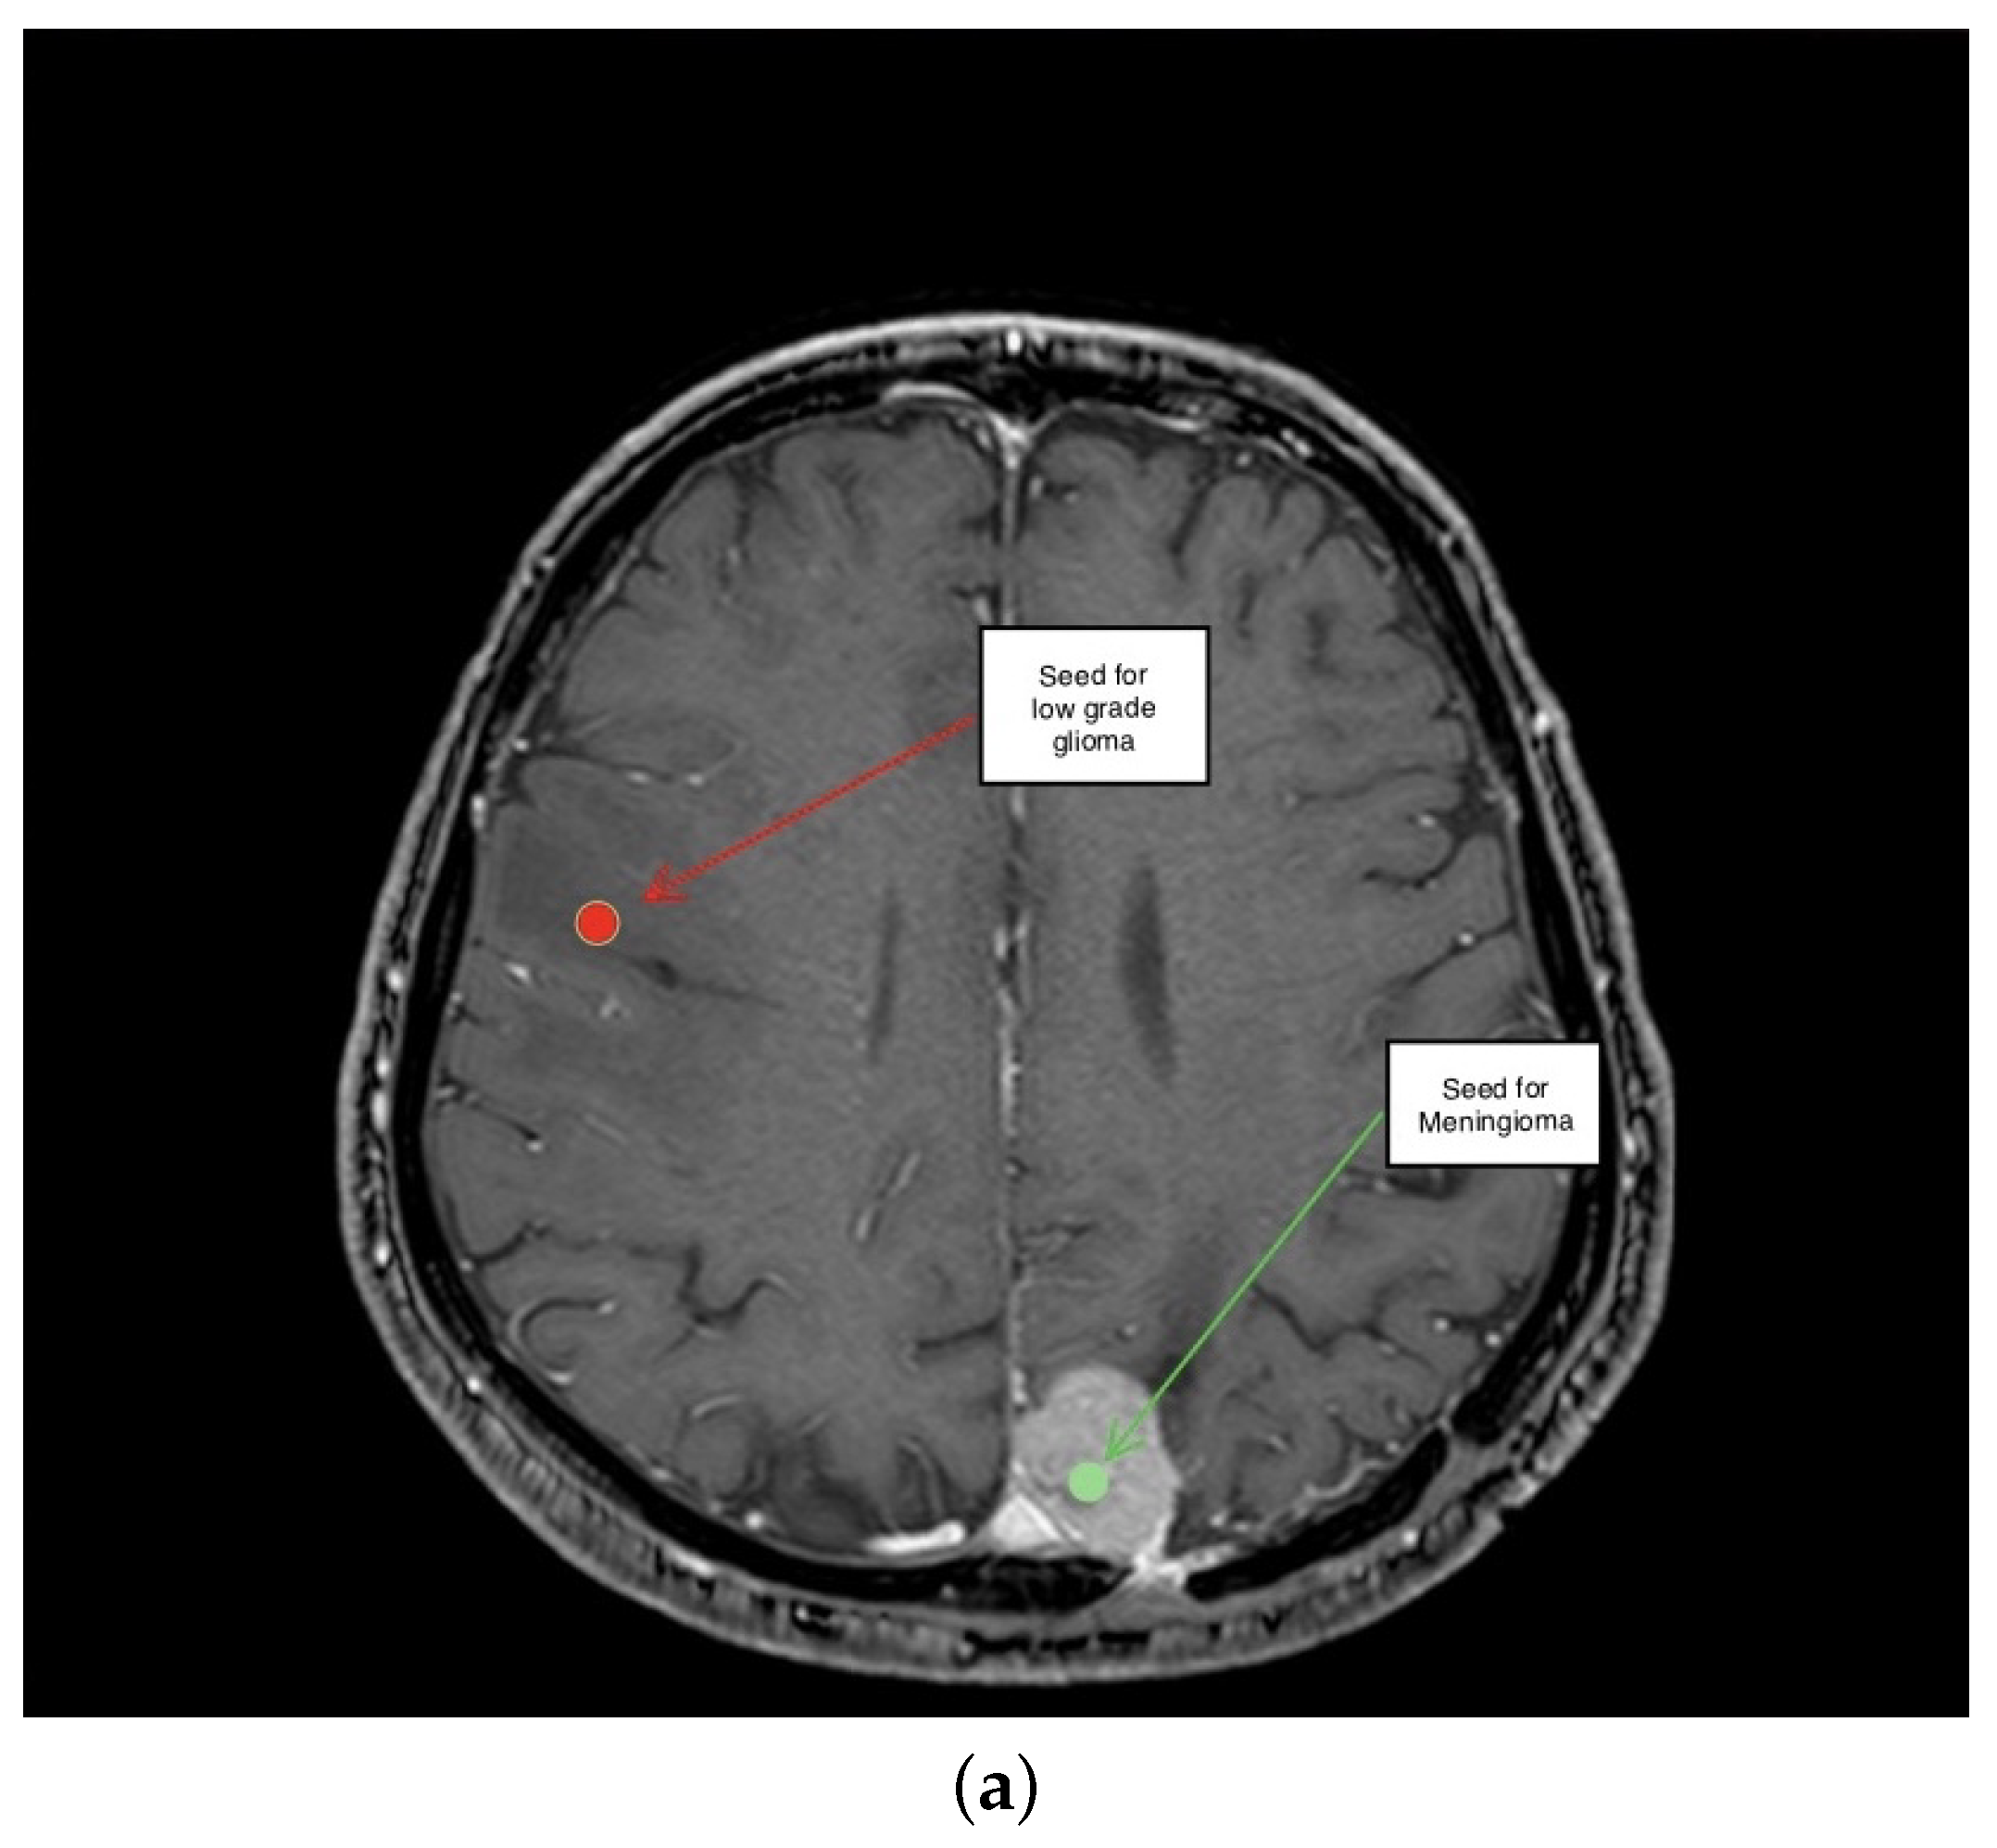

3.1. First Scenario

3.2. Second Scenario

3.3. Third Scenario